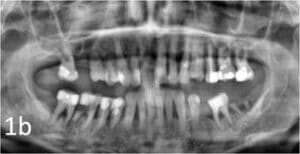

Une patiente de 55 ans, en bonne santé et non fumeuse, présentait une mobilité dentaire généralisée et une récession gingivale. Des examens cliniques et radiologiques (Fig. 1a, 1b) ont été réalisés. Un diagnostic de parodontite généralisée de stade 3, grade B 2, a été posé. La maladie parodontale a été traitée et l’état maxillaire a été stabilisé par un traitement endodontique et la pose de bridges provisoires.